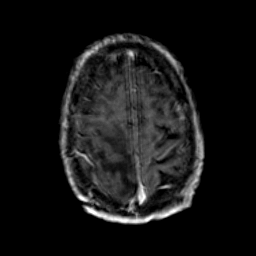

Glioma Overlay -- Slice #17

[Home][Help][Clinical] Slice 17